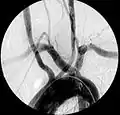

Aberrant right subclavian artery at angiography.